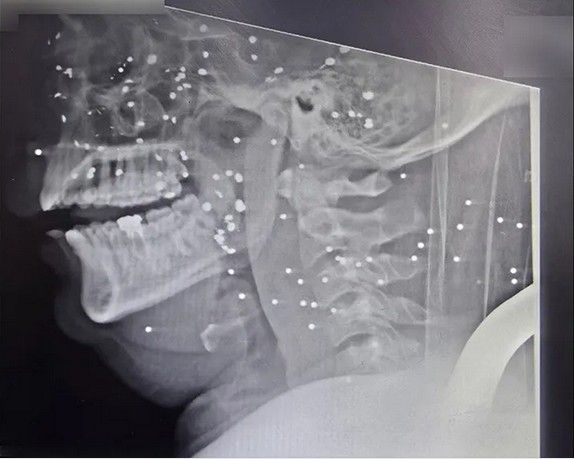

تصاویر رادیوگرافی معترضان نشان میدهد صورت انسانها به هدف تیراندازی تبدیل شدهاند. در چندین پرونده، صورت و سر مجروحان با دهها ساچمه فلزی پر شده است؛ ساچمههایی که در بافت نرم صورت، اطراف چشمها، بینی، فک و حتی نزدیکی جمجمه گیر کردهاند. این الگو با شلیکهای پراکنده و تصادفی همخوانی ندارد و بیشتر شبیه شلیک مستقیم و از فاصله نزدیک به چهره انسانهاست.

در تصویر رادیوگرافی سه تن از معترضان مجروح دیده میشود که در ناحیه سر، صورت و گردن هر کدام حدود ۱۰۰ ساچمه وجود دارد. تعداد ساچمهها در کنار پراکندگی وسیع، اندازه ریز و یکنواخت آنها و نفوذ برخی ساچمهها به جمجمه و بافتهای عمقی صورت، با مشخصات فشنگهای ساچمهریز (Birdshot) تطابق دارد. بر اساس اطلاعات پرونده این بیماران مجروحانی که در عکسهای شماره ۱ و ۲ رادیوگرافی آنها منتشر شده، پس از چند روز جان خود را از دست دادهاند.

«کیانا کثیری»، متخصص پزشک خانواده، که خود نیز در گروههای درمانی در جریان اعتراضات «زن زندگی آزادی» و همچنین اعتراضات دیماه امسال فعالیت داشته، در مورد این سه آسیبدیدگی میگوید: «این سه مجروح مورد اصابت تعداد متعدد ساچمه قرار گرفتند که بدون شک اندام چشم آسیب دیده، این مجروحان دچار التهاب و عفونت در ناحیه بافت گوشتی سر و صورت خواهند شد. از آنجا که در ناحیه صورت تمرکز رگهای خونی و رشتههای عصبی فوق العاده زیاد است، این مجروحان دچار دردهای فوقالعاده شدید خواهند شد که متاسفانه عمل جویدن و بلع را مختل میکند.

در مورد آسیب چشمی باید دید که آسیبدیدگی در چه حد و میزانی است. متاسفانه اگر درمان سریع انجام نشود و چشم عفونت کند مجبور به تخلیه چشم خواهند شد. در هر صورت آسیبدیدگی چشمی حاصل از اصابت ساچمهها باعث ضعف شدید قدرت بینایی خواهند شد.»